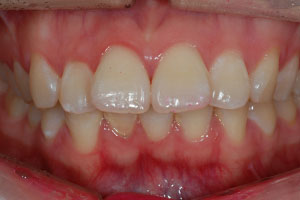

치료증례 전후사진

Before & After